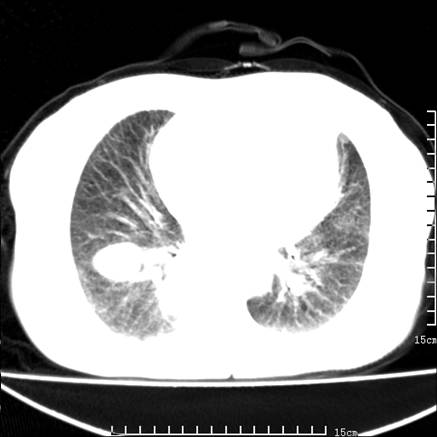

女,王某,58岁,咳嗽三个月余,基层医院二个月前诊为肺结核,用抗结核药二个月无明显疗效。

心包积液致肺瘀血.右侧周围型肺癌伴肺内转移,中间裂积液,叶间胸膜肥厚.右上肺大泡,右侧胸膜肥厚.

双肺继发型tb,心功能不全并肺淤血、心包、双侧叶间裂积液,肺大泡,右下胸膜肥厚钙化。